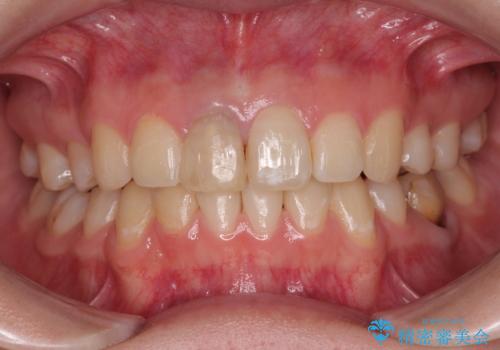

神経を取って変色した歯 オールセラミッククラウンで綺麗に仕上げる

明るく自然な口元になりました。